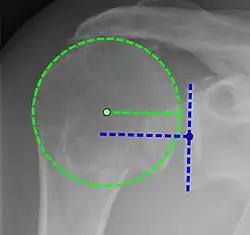

Xray

Projectional radiograph of normal glenohumeral position.[51]

High-riding humeral head in a rotator cuff tear.

X-ray projectional radiography cannot directly reveal tears of the rotator cuff, a 'soft tissue', and consequently, normal X-rays cannot exclude a damaged cuff. However, indirect evidence of pathology may be seen in instances where one or more of the tendons has undergone degenerative calcification (calcific tendinitis). The humeral head may migrate upward (high-riding humeral head) secondary to tears of the infraspinatus, or combined tears of the supraspinatus and infraspinatus.[51] The migration can be measured by the distance between:

• A line crossing the center of a line between the superior and inferior rims of the glenoid articular surface (blue in image).

• The center of a "best-fit" circle positioned over the humeral articular surface (green in image)

Normally, the former is positioned inferiorly to the latter, and a reversal therefore indicates a rotator cuff tear.[51] Prolonged contact between a high-riding humeral head and the acromion above it may lead to X-ray findings of wear on the humeral head and acromion; secondary degenerative arthritis of the glenohumeral joint (the ball and socket joint of the shoulder), called cuff arthropathy, may follow.[50] Incidental X-ray findings of bone spurs at the adjacent acromioclavicular joint may show a bone spur growing from the outer edge of the clavicle downward toward the rotator cuff. Spurs may also be seen on the underside of the acromion, once thought to cause direct fraying of the rotator cuff from contact friction, a concept currently regarded as controversial.